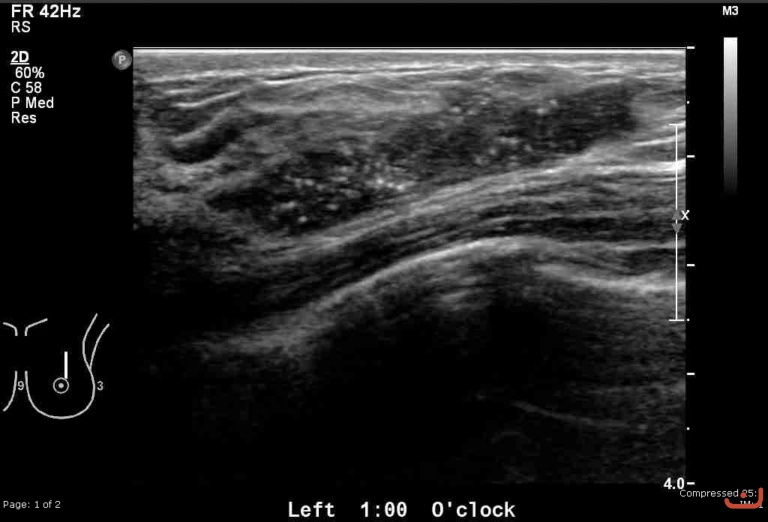

Malignant solid mass

Thursday, 30 April 2015

156.83 KB (768 x 522 px)